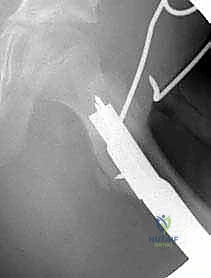

- الأشعة السينية الرقمية (Digital X-Rays): أخذ صور بوضعيات متعددة (أمامي خلفي، وضعية الضفدع) لقياس "زاوية عنق الفخذ-الجذع" بدقة متناهية، وحساب نسبة التغطية الحُقية.

3. إدخال سلك الدليل (Guide Wire Placement)

هذه هي الخطوة الأكثر أهمية. باستخدام الأشعة المباشرة، يقوم الدكتور بإدخال سلك معدني رفيع في عنق عظم الفخذ باتجاه الرأس. يتم وضع هذا السلك بزاوية محسوبة مسبقاً بدقة متناهية لتتطابق مع زاوية الشريحة (90 درجة).

5. قطع العظم (The Osteotomy)

باستخدام منشار جراحي عالي الدقة، يقوم الدكتور هطيف بقطع عظم الفخذ أسفل منطقة المدور الكبير (Subtrochanteric). في هذه المرحلة، يتم إزالة إسفين عظمي صغير (Wedge) بالزاوية المطلوبة لتصحيح التشوه.